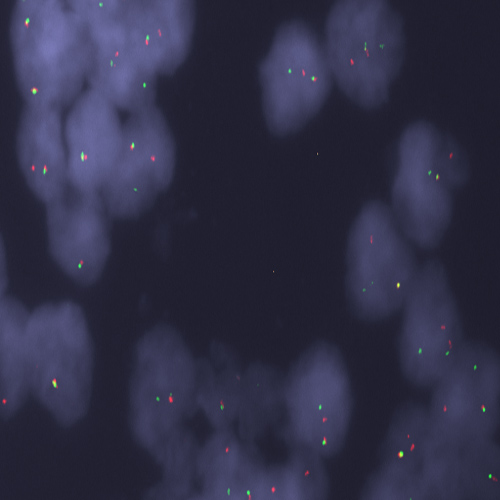

Mantle Cell Lymphoma stained using CCND1 (11q13) Break – XL for BOND (KBI-XL013).

The CCND1 (11q13) Break - XL for BOND FISH probe detects genomic translocations involving the CCND1 gene. CCND1 (11q13) Proximal - XL and CCND1 (11q13) Distal - XL are optimized to detect genomic regions proximal and distal to break points in the CCND1 gene region.

When combined, both probes are used to detect translocations involving the CCND1 gene at 11q13.